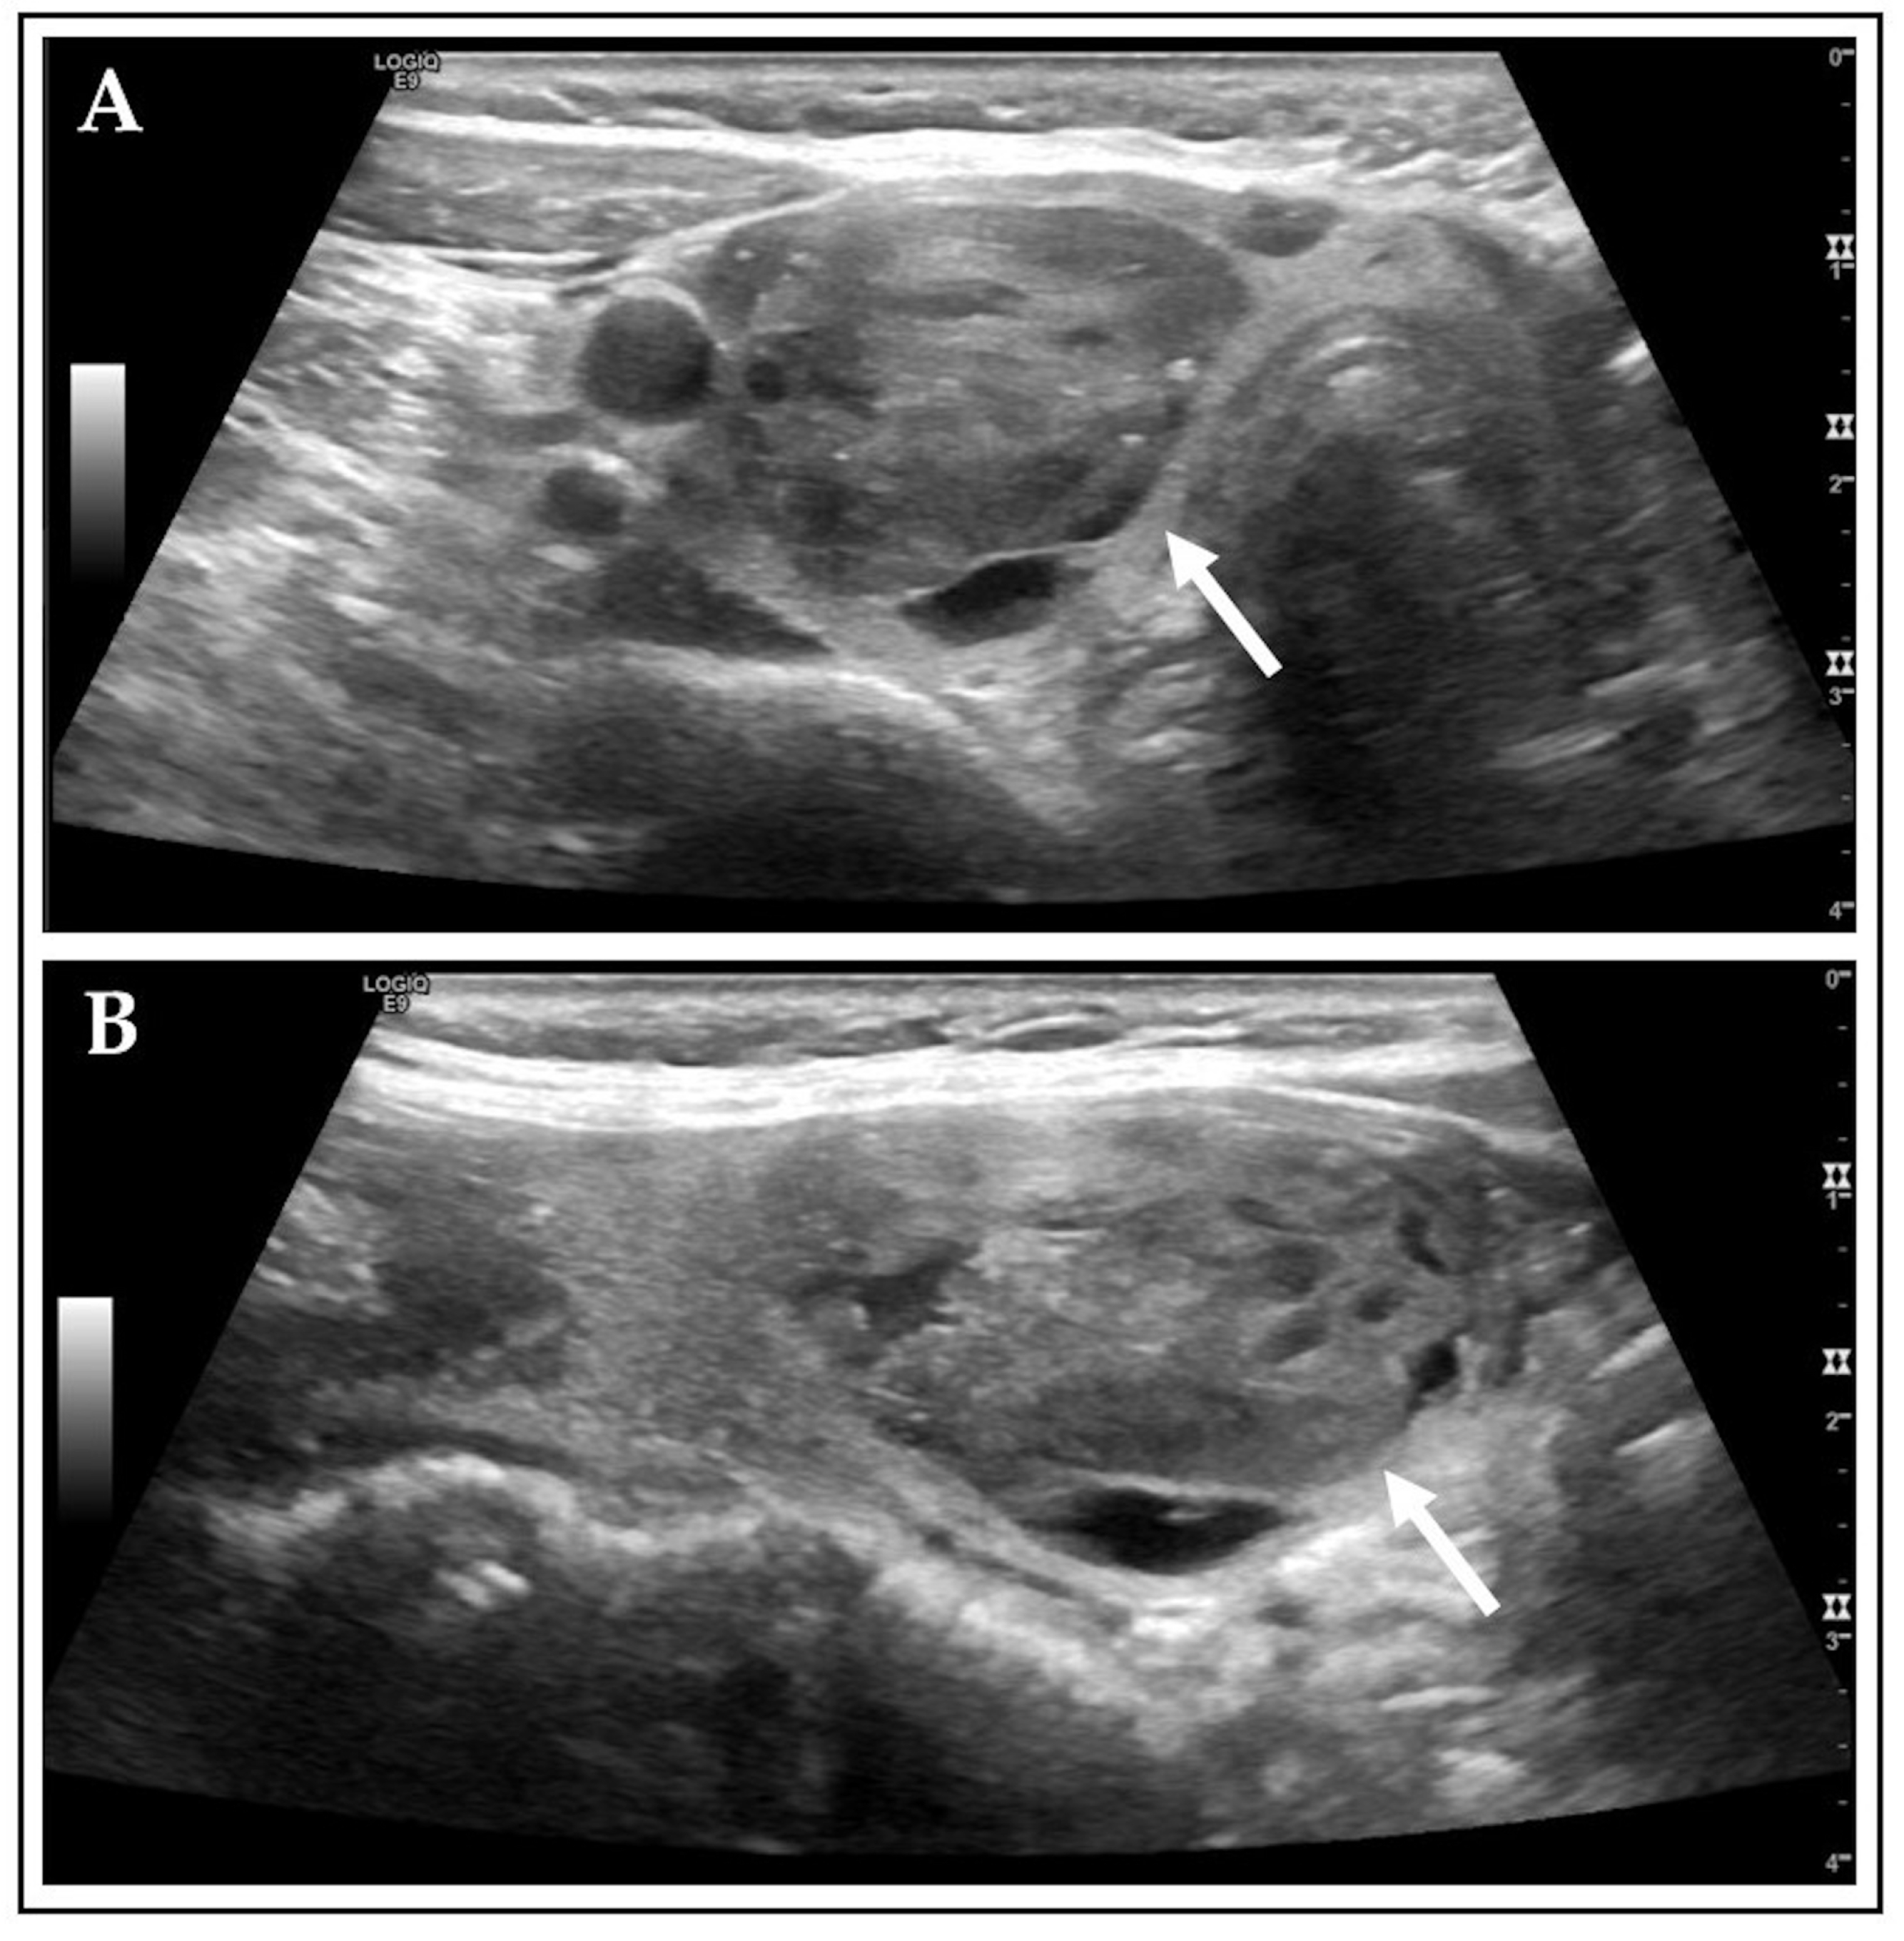

| None | 52 (12.3) | 102 (24.1) | p < 0.001 | rs = 0.603 p < 0.001 |

| Large comet-tail artifacts | 350 (82.5) | 280 (66.0) | p < 0.001 | |

| Macrocalcifications | 145 (34.2) | 109 (25.7) | p = 0.007 | |